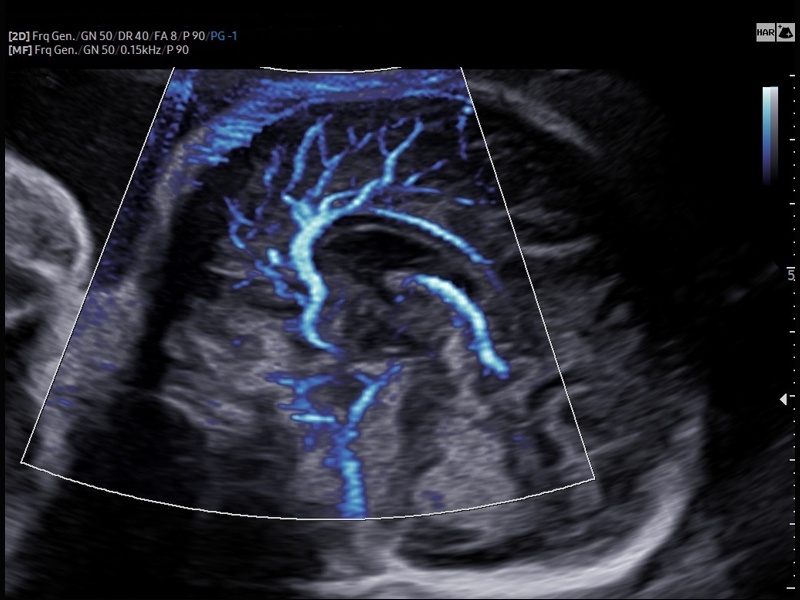

• Модуль MV-Flow – программа (режим), позволяющая визуализировать кровоток в микроциркуляторном русле с высоким разрешением без использования контраста.

• Модуль LumiFlow – программа отображения кровотока с объемной графикой для лучшего понимания архитектоники сосудистого русла.

• Программа SEE Stream – режим недопплеровской визуализации кровотока в реальном масштабе времени.

• Модуль MV-Flow - программа (режим), позволяющая визуализировать кровоток в микроциркуляторном русле с высоким разрешением без использования контраста.